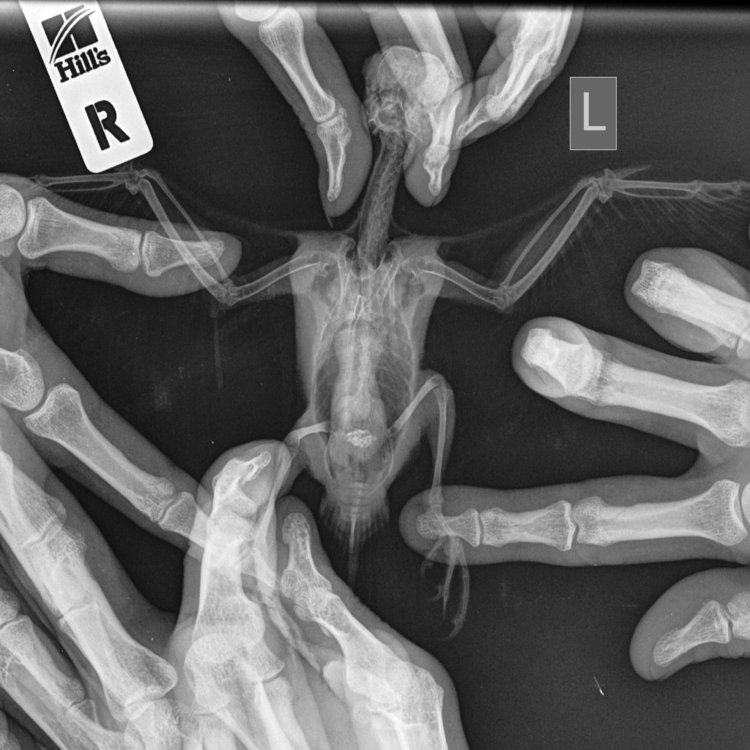

8.1. какие исследования, где и как давно проводились; анализ кала 21.04, рентген 23.04

про кал знаю только что большое количество лейкоцитов, больше подробностей врач не сообщила, рентген приложу ниже

Мелкие+животные_Рептилии-Брюшная+полость+VD-23.04.2020-18_59_36-135.JPEG

Мелкие+животные_Рептилии-Брюшная+полость+VD-23.04.2020-18_59_36-322.JPEG

На снимке- как бы все относительно неплохо, хотя есть следы воспалительного процесса в легких, и ярковаты почки.